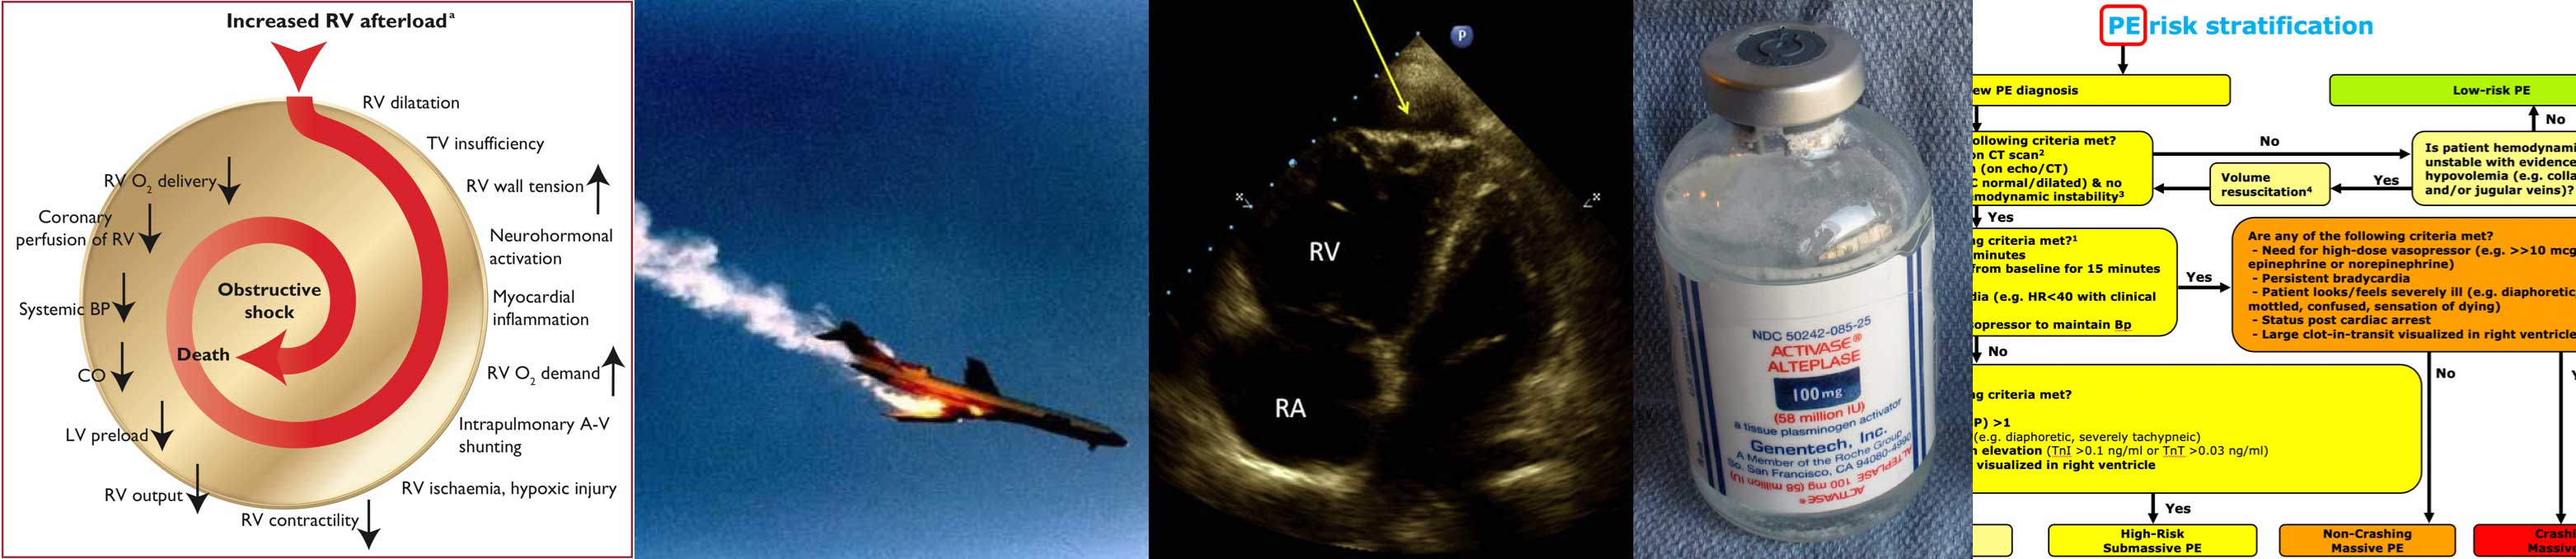

Submassive & Massive PE - EMCrit Project

Pulmonary embolism - Wikipedia